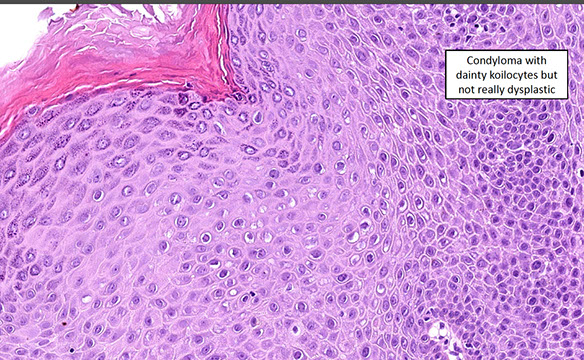

Anal Intraepithelial Neoplasia (AIN)